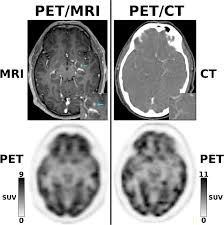

Mri Vs Pet Scan Which One You Should Get And Why from post.healthline.com Pet scans (positron emission tomography scans) are often done in conjunction with ct scans (computerized tomography scans) or mri scans (magnetic resonance imaging scans). Diffen › health › diagnostics. Positron emission tomography (pet) imaging scans use a radioactive tracer to check for signs of cancer, heart disease and brain disorders. Ct scan costs range from $1,200 to $3,200; Primarily a medical imaging technique most commonly used in. A pet scan allows physicians to measure the body's abnormal molecular cell activity mri: A ct scan (or cat scan) is finest matched for diagnosing bone injuries, identifying lung and chest difficulties, and sensing cancers. Mike shows you how they are both used and sheds light on what an mri, cat scan (ct scan), and a pet scan is.

Computed axial tomography (cat or ct) was introduced in. Mike shows you how they are both used and sheds light on what an mri, cat scan (ct scan), and a pet scan is. At health images, we use the latest ct scan technology to get patients in and out of the. Some hospitals now use a hybrid pet/mri scan. A ct scan (or cat scan) is finest matched for diagnosing bone injuries, identifying lung and chest difficulties, and sensing cancers. Pet scans (positron emission tomography scans) are often done in conjunction with ct scans (computerized tomography scans) or mri scans (magnetic resonance imaging scans). The person lies on a table that moves through a scanning ring our doctors use advanced imaging tests, such as ct scans, mris, and pet scans, to help detect and diagnose disease, make appropriate treatment. .scan and an mri scan however, when i was first diagnosed, i was sent for a pet scan as supposedly, these show more detail. Image slices that ct scans produce can be 2 or 3 dimensional and can reveal abnormal structures or help the physician plan and moni. What is the main difference between ct scan and mri and which one is best. Ct scan costs range from $1,200 to $3,200; How does a ct scan (cat scan) work? Some patients find an mri claustrophobic.

What S The Difference Between All The Different Head Scans X Ray Ct Mri Mra Pet Scan San Diego Brain Injury Foundation from sdbif.org A ct scan (or cat scan) is finest matched for diagnosing bone injuries, identifying lung and chest difficulties, and sensing cancers. Some hospitals now use a hybrid pet/mri scan. Ct scans and mri scans are two medical imaging methods that create detailed images of internal body parts, including bones, joints, and organs. An animation i made describing the differences between these three scans'. Mri does not use radiation. Some patients find an mri claustrophobic. How do mri, pet and cat scans work? The person lies on a table that moves through a scanning ring our doctors use advanced imaging tests, such as ct scans, mris, and pet scans, to help detect and diagnose disease, make appropriate treatment.

Some hospitals now use a hybrid pet/mri scan. Ct scan costs range from $1,200 to $3,200; How does a ct scan (cat scan) work? Mri scan is very noisy and you will be given earplugs or headphones. There is no radiation hazard risk for the patients undergoing an mri scan.

Difference between cat scan and mri электронный ресурс. Some hospitals now use a hybrid pet/mri scan. How do mri, pet and cat scans work? At health images, we use the latest ct scan technology to get patients in and out of the. Ct was developed independently by a british engineer named sir godfrey hounsfield and dr. Pet scans (positron emission tomography scans) are often done in conjunction with ct scans (computerized tomography scans) or mri scans (magnetic resonance imaging scans). What is the difference between mri and pet scans? Submitted 1 year ago by cfern074. They usually cost less than mris (about half the price of mri). Does anybody have a good way to explain the difference? A ct scan (or cat scan) is finest matched for diagnosing bone injuries, identifying lung and chest difficulties, and sensing cancers. Positron emission tomography (pet) imaging scans use a radioactive tracer to check for signs of cancer, heart disease and brain disorders. Much higher than regular ct scans.